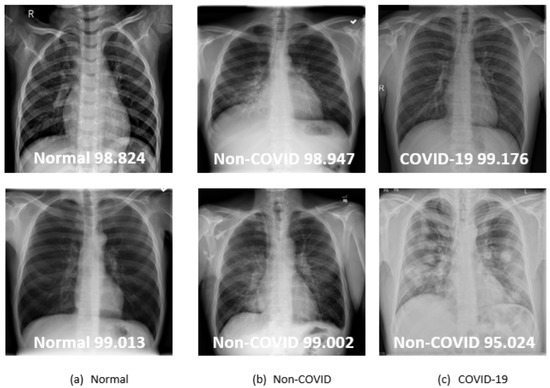

The COVID-QU-Ex collection consists of three categories: normal, non-COVID infection, and COVID-19. Patients with normal (healthy) situations represent 32% of the total collection with 10,701 instances, non-COVID infection situations represent 33% with 11,263 instances, and COVID-19 situations represent 35% with 11,956 instances. These images represent two different diseases and one healthy state. Each image’s resolution in the collection, which is in a PNG file format, is 256 pixels per flank. Figure 1 illustrates a sample of a normal instance and two distinct disorders that may damage the lungs. Since the collection is already large and relatively well-balanced, as shown in Figure 2, there is no need to use data augmentation techniques to make it more balanced.

From the radiographic findings in Figure 1, a normal lung X-ray typically shows clear lung fields without any significant opacities or abnormalities. The lung markings appear normal, with the blood vessels and airway passages clearly visible. In cases of viral or bacterial pneumonia, the X-ray image often reveals areas of opacity or consolidation. These areas appear as dense, cloudy regions within the lung fields, indicating the presence of inflammation, fluid, or pus. The opacities can be patchy, focal, or lobar, depending on the severity and extent of the infection. X-ray findings in COVID-19 pneumonia show ground glass opacities (blurry areas) in multiple areas of the lungs. These opacities often have a peripheral distribution and can affect both lungs symmetrically [29,30].

Figure 1. X-ray samples by category from the COVID-QU-Ex collection (the white markers indicate infected areas).